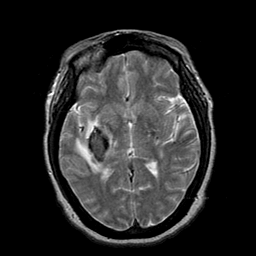

Cerebral hemorrhage, MR Study mr-t2 -- Slice #12

[Home][Help][Clinical] Slice 12